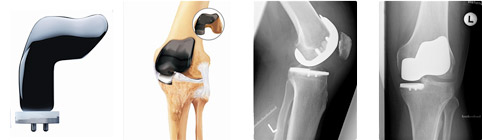

PROTESI MONOCOMPARTIMENTALI

- Il ginocchio è diviso in tre compartimenti principali: il compartimento mediale (la parte interna del ginocchio), il compartimento laterale (la parte esterna) e il compartimento femoro-rotuleo (la parte anteriore del ginocchio tra il femore e la rotula).

In casi selezionati, pazienti con un’artrosi localizzata ad un solo compartimento del ginocchio (generalmente quello interno o mediale) possono essere candidati per una protesi monocompartimentale in cui solo la porzione del ginocchio danneggiata viene sostituita dalle componenti protesiche.

I vantaggi di questo tipo di protesi sono rappresentati da una minor invasività, dalla preservazione dei legamenti e quindi di una più fisiologica biomeccanica del ginocchio che si traduce in una ripresa più veloce e in un recupero migliore della funzionalità.

Sono state recentemente introdotte anche protesi cosiddette bicompartimentali (Duece) che permettono la sostituzione sia del compartimento femoro-rotuleo che di quello mediale.

PROTESI TOTALI (DI RIVESTIMENTO) - Si tratta del tipo di protesi più comunemente usato. Si definisce “di rivestimento” in quanto la protesi “riveste” i capi articolari da cui sono stati asportati la cartilagine danneggiata e parte dell’osso sottostante. Apposite mascherine di taglio vengono applicate su tibia e femore e guidano le resezioni ossee in modo che il femore, la tibia ed eventualmente la rotula vengano preparati per accogliere la protesi.